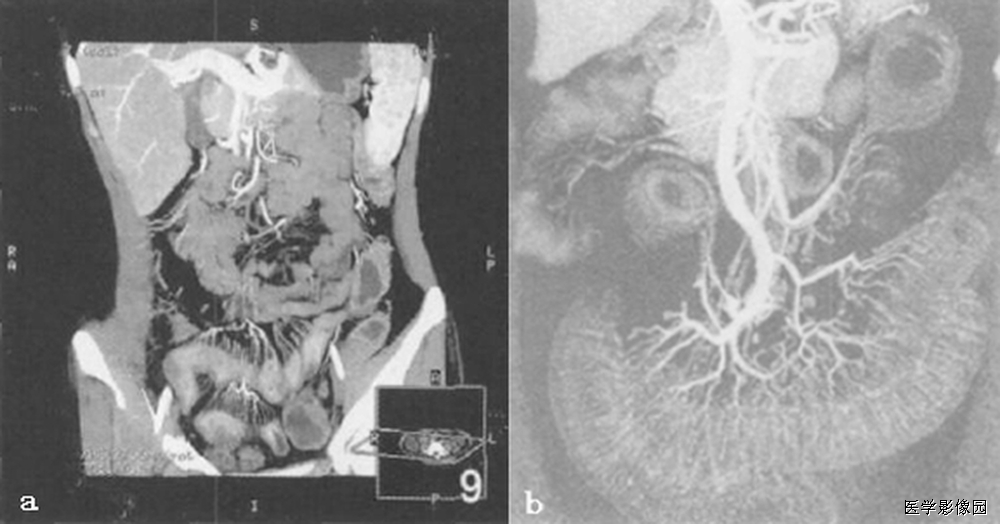

13、三明治征(夹心面包征或夹心饼征)

指2个均质软组织肿物组成三明治面包,系膜脂肪和管状物为构成夹心,是腹部CT横断扫描时的影像表现。系膜脂肪和血管组成夹心,肿大淋巴结组成面包;在给予增强剂后系膜管状结构(血管、肠管)相对脂肪增强,夹心层突出。因为淋巴结增大会压迫血管,阻碍静脉回流,使夹心层内增强的血管更加明显。

当经静脉及口服造影剂后,肠系膜血管结构较脂肪明显强化,从而可使夹心更加突出。导致肠系膜淋巴结肿大的病因很多。除淋巴瘤外,癌、肉瘤、类癌、获得性免疫缺陷相关性淋巴结增生综合征、结核、肠源性脂肪代谢碍及炎症性肠病等也是最常的病因。

三明治征为肠系膜淋巴瘤的特异征象。因为只有在肠系膜淋巴瘤中淋巴结才可以长得很大,并包绕脂肪、肠管和血管而不产生任何临床症状。肠系膜淋巴瘤偶尔可侵犯浆膜及固有肌层,有时会引起小肠出血但极少引起游离性穿孔。肠系膜淋巴瘤还可以引起腹膜后淋巴结肿大。

总之,三明治征指的是CT柏横断面上,巨大增生的肠系膜淋巴结包绕肠系膜脂肪和血管而形成的类似三明治的影像。对于设有移植病史的患者,非霍奇金淋巴瘤是三明治征的主要病因;有移植病史的患者,产生三明治征的原因则可能是淋巴组织增生性疾病,随着接受移植手术的患者不断增多,三明治征可能会在临床上越来越常见。

下图是一个恶性肿瘤腹膜后淋巴结转移患者:

下边两幅图更典型:

图1:非何杰金淋巴瘤患者口服造影剂后增强CT横断面。显示2个巨大系膜淋巴肿物(2个面包-带尾箭头),包绕中心系膜和增强的血管。注意增强的小肠位于周边,腹膜后淋巴结显著增生-箭头)。

图2:患者6个月前曾行左肾移植发现PTLD,血管和口服造影剂横断CT显示三明治征——系膜淋巴肿物(实心带尾箭头),靠近右肾(箭头),有腹膜淋巴结肿大(空心带尾箭头)。